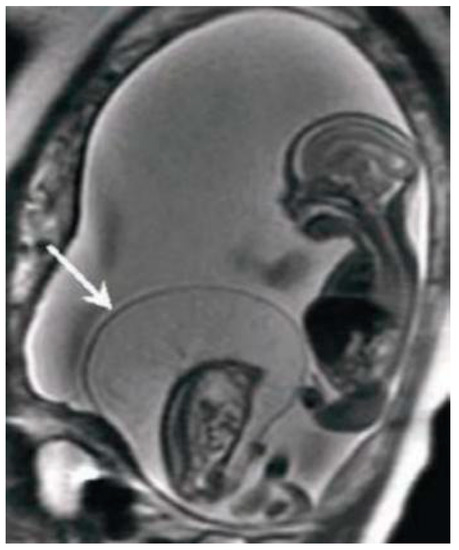

Figure 2.

Diffusion Weighted Imaging (DWI).